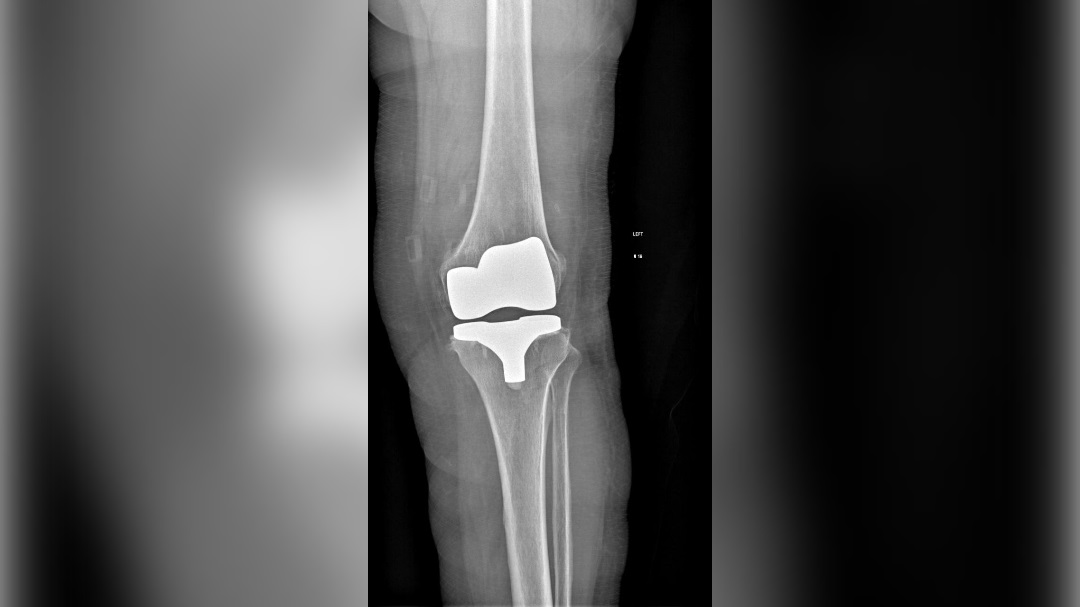

Врачи Воронежской городской клинической больницы скорой медицинской помощи (ВГКБСМП) №1 помогли 75-летней пациентке с двусторонним гонартрозом коленных суставов последней стадии вернуться к активной жизни. Гонартроз – это заболевание, при котором происходит изнашивание и разрушение хряща в коленном суставе. Из-за разрушения хряща кости начинают тереться друг об друга, это вызывает боль, скованность в колене, хруст при сгибании, отек. Женщине провели эндопротезирование коленных суставов (имплантация устройства, которое имеет функцию здорового сустава. – Прим. ред.). Об этом сообщили в больнице в четверг, 10 апреля.

Эндопротезирование левого коленного сустава пациентке выполнили в декабре 2023 года. Операция прошла успешно. В январе 2025 года пациентке провели эндопротезирование правого коленного сустава. Операцию проводили травматологи-ортопеды Евгений Яшников и Сергей Курьянов, медсестра Ирина Поваляева, анестезиолог-реаниматолог Елена Чурсанова и медсестра-анестезист Галина Сухотерина. Операция прошла без осложнений, и уже через несколько дней женщина делала первые шаги под присмотром лечащего врача и реабилитологов. Сейчас пенсионерку уже выписали, она чувствует себя хорошо.